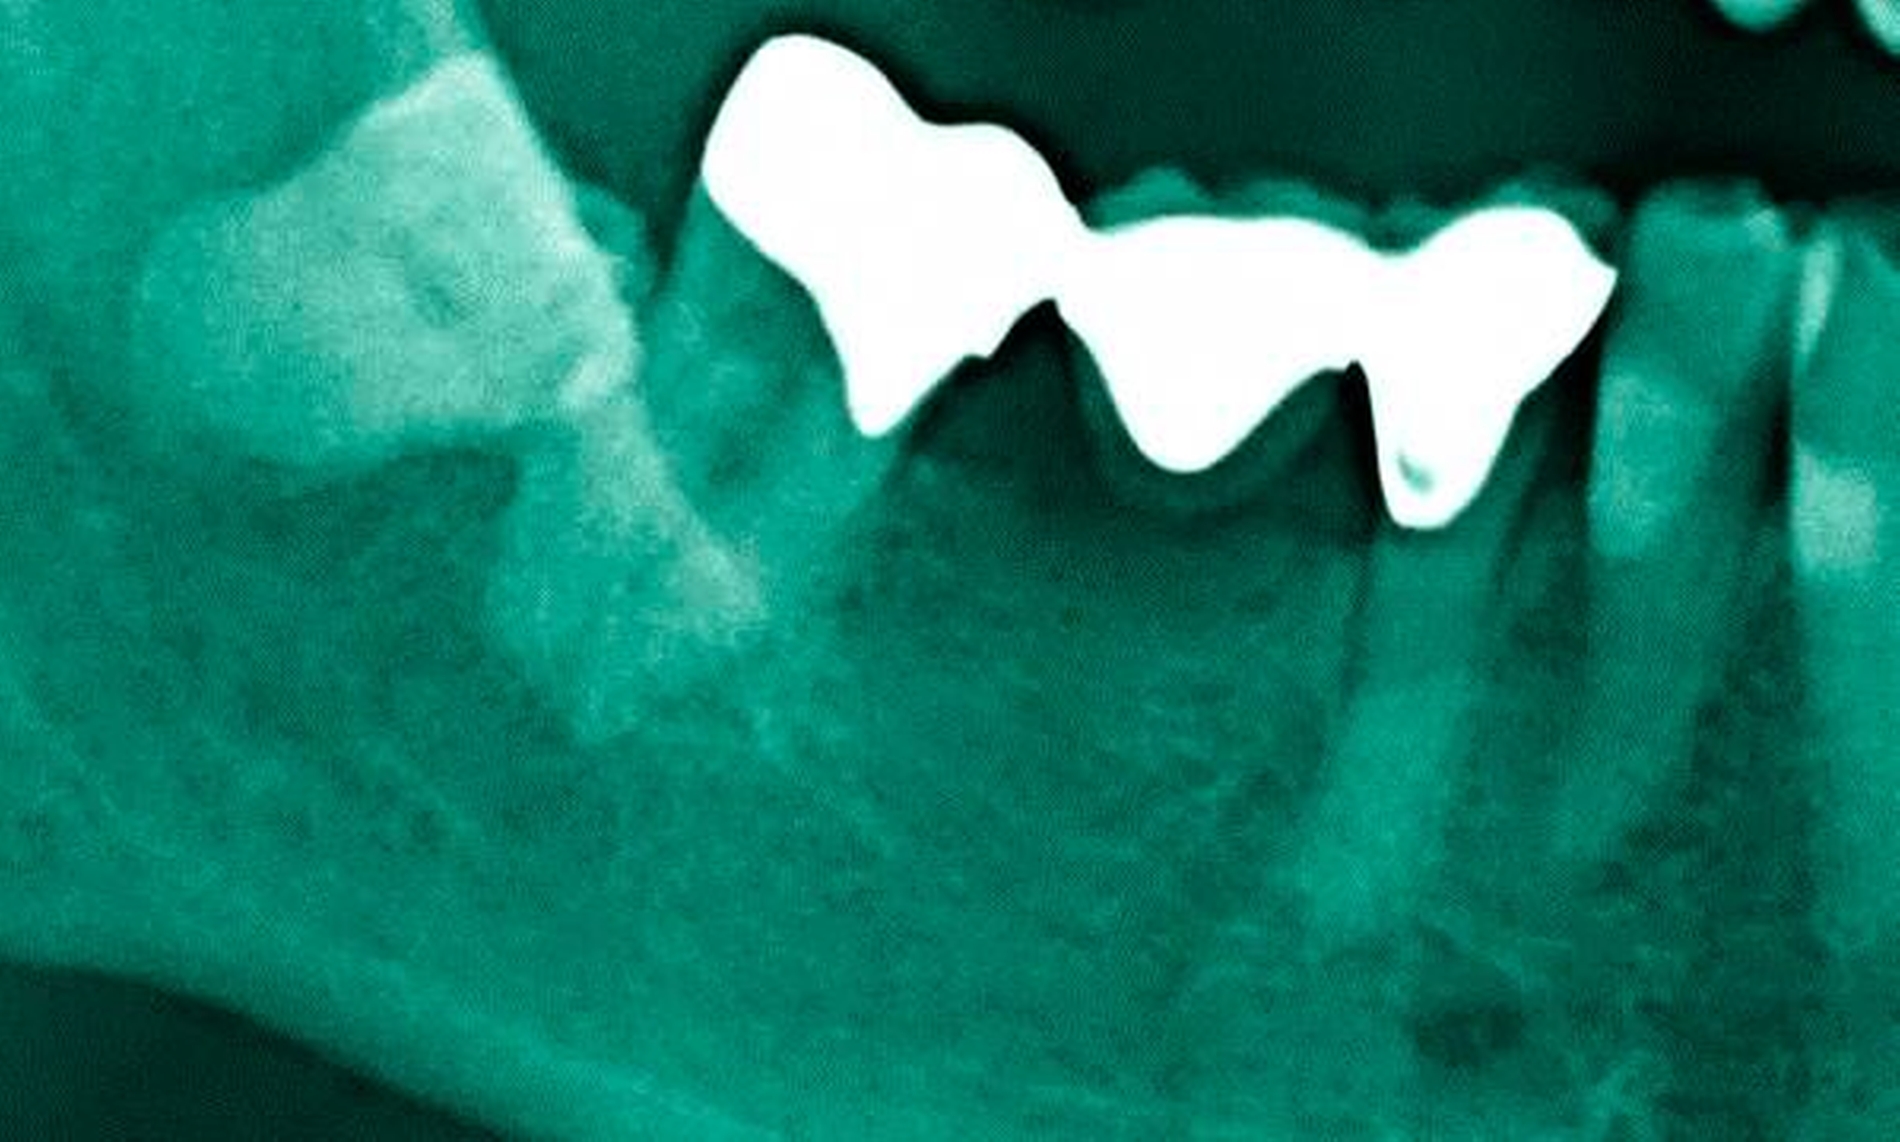

Abbildung 4: Anliegen eines 76,5-jährigen Patienten (Anfrage per E-Mail). Zitat: „Mich plagt eine … Entzündung des Mundraums, die auch das Zahnfleisch meiner Zahnstummel angreift, weshalb ich nur noch Breiartiges zu essen vermag. Ein Angsthase wie ich geht zum Zahnarzt NUR unter dem Eindruck akuter Schmerzen!“

Damit wird die Hygienefähigkeit zumindest partiell verbessert und Spielraum für künftige Planungen und Vorgehensweisen unter besseren Bedingungen belassen. Das Procedere ist in den Abbildungen 4 und 5 beschrieben. Bei dem in Abbildung 4 vorgestellten Patienten lag eine Oralphobie im Seniorenalter vor. Die Verlaufsbeschreibung macht deutlich, dass selbst im fortgeschrittenen Alter eine Adaptation an zahnärztliche Interventionen im Einzelfall noch möglich ist.

4. Vorgehen bei frakturierten Zahnkronen/Wurzelresten

Üblicherweise werden frakturierte Zahnkronen beziehungsweise Wurzelreste restaurativ wieder aufgebaut oder es erfolgt eine Extraktion. Im Seniorenalter erscheint es hingegen manchmal als Kompromissmaßnahme vertretbar, Wurzelreste vorerst zu belassen und etwa mit adhäsiv eingebrachtem Komposit knapp über Gingivahöhe abzudecken. Dies bietet sich vor allem dann an, wenn die Wurzelkanäle bereits obliteriert und endodontische Interventionen nicht erforderlich sind (Tabelle 4) [Staehle et al., 2017].